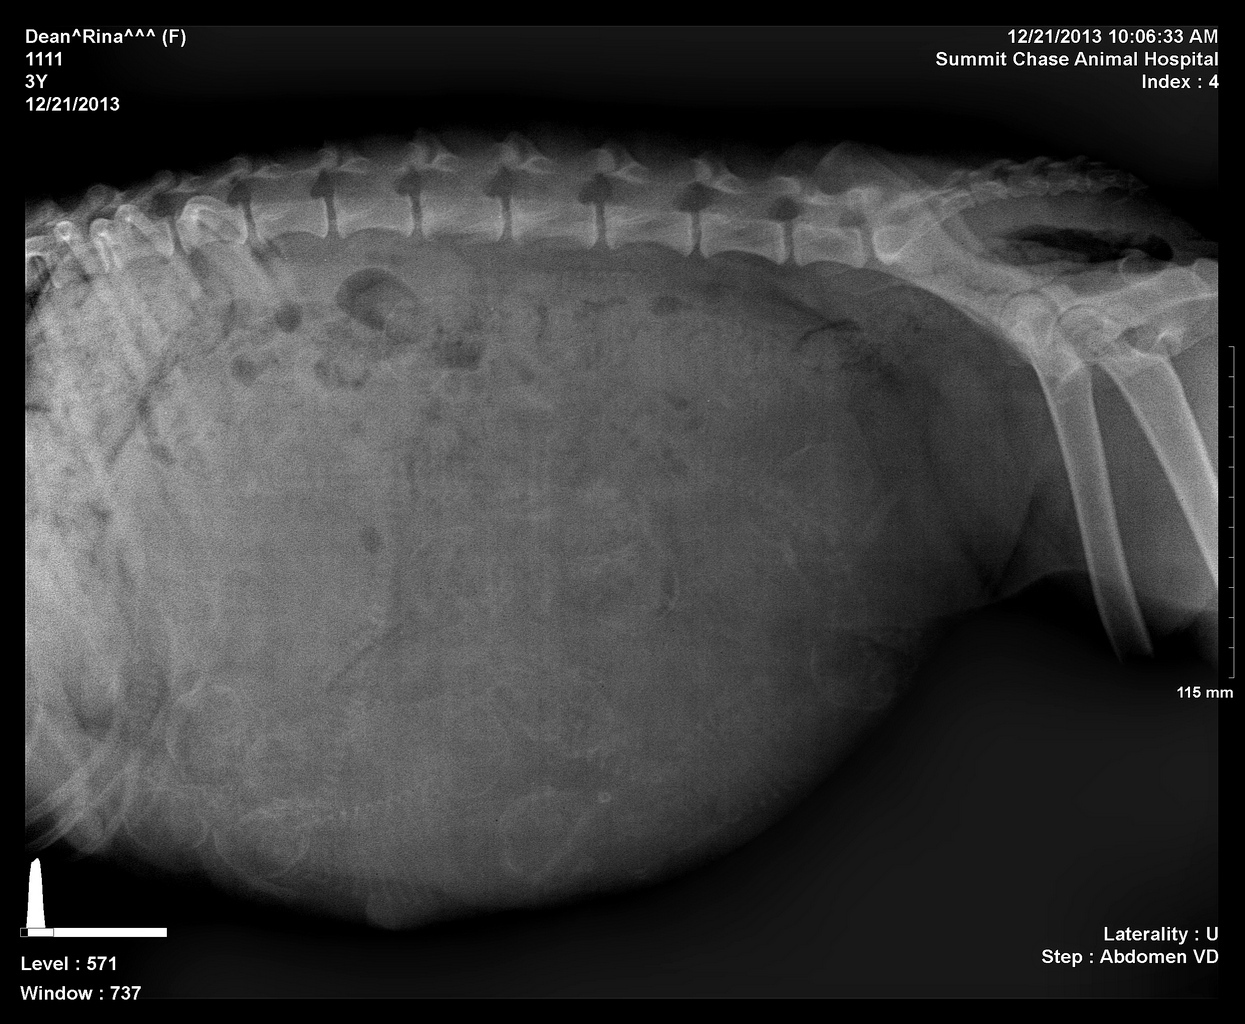

Rina preg 2 day 54

Tough to count try to click the x to make it bigger...looking like 7-8...counting heads and spines.